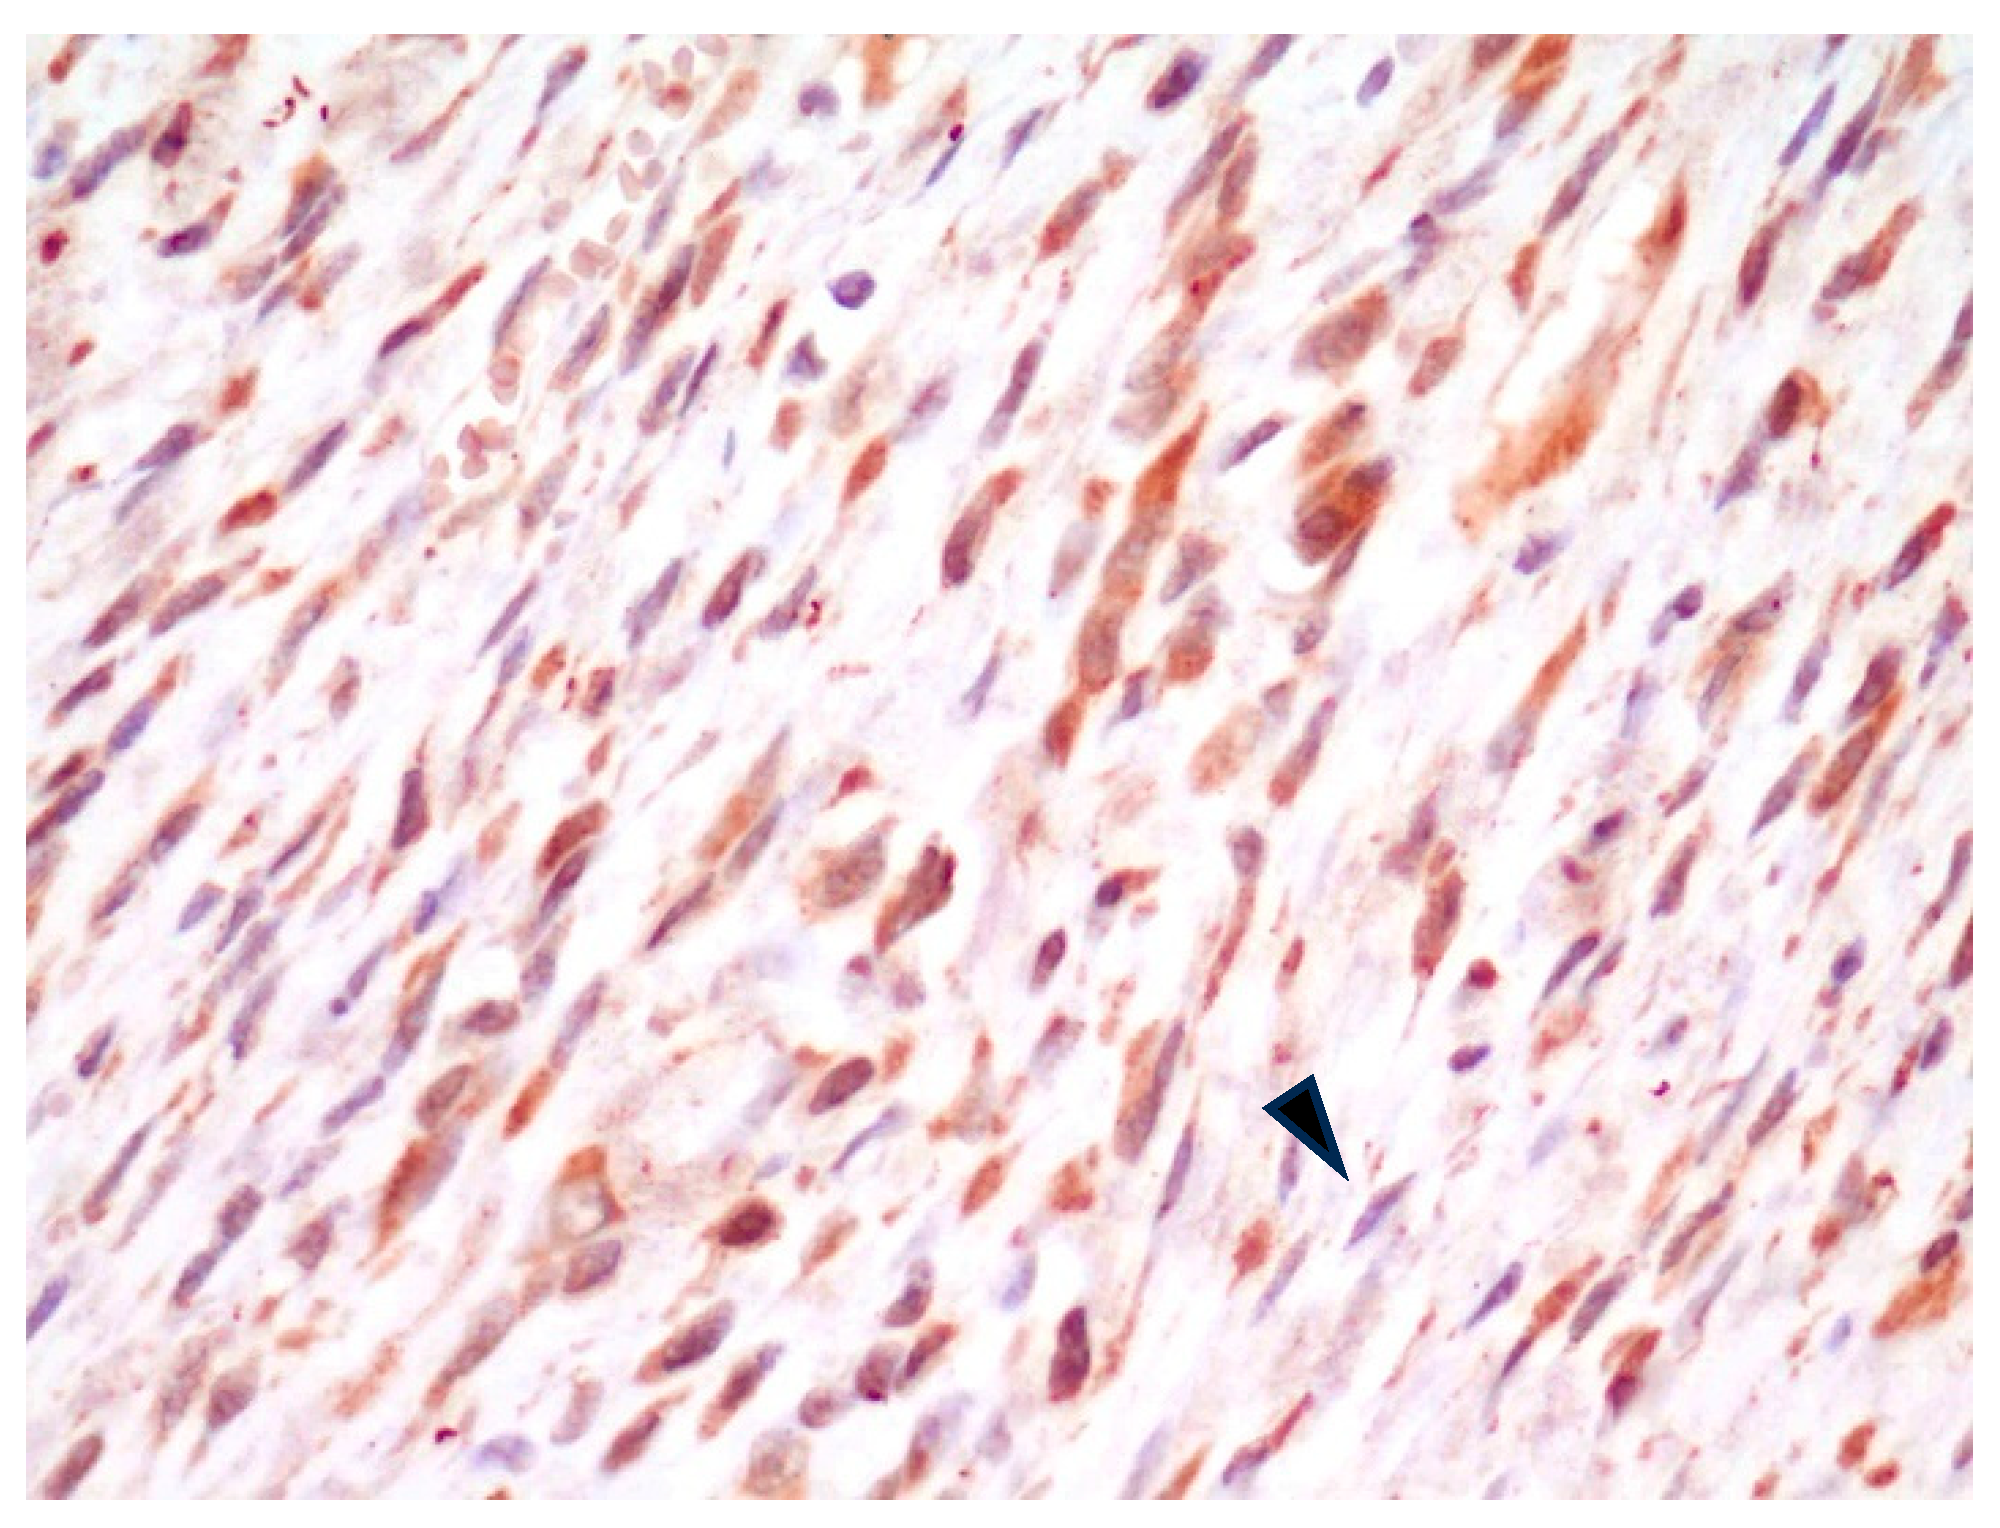

All FISS were positive for αv integrin (Table 1) with a variable pattern of cell staining. Specifically, in 7/7 fibrosarcomas, spindle neoplastic cells were characterized by mild-to-moderate cytoplasmic positive immunostaining (Figure 1). Nuclear positivity was occasionally noted in the same cells and interpreted as non-specific.

Figure 1.

FISS, fibrosarcoma. Moderate cytoplasmic positivity for αv integrin. Note the presence of at least 2 mitotic figures in the field (arrowheads). IHC for αv integrin, 400×.